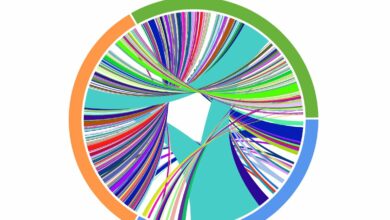

Um gráfico de Circos representando os resultados do sequenciamento de receptores de células T correspondentes coletados em um paciente submetido…